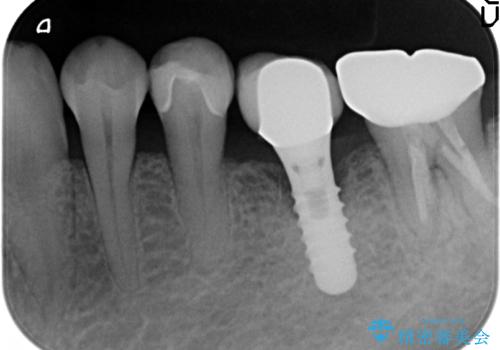

- 左下5番目の銀歯が気になるのでセラミックにしたいといらっしゃった方の症例です。

銀歯及び虫歯を除去後、セラミックインレーによる修復を行いました。

当院のセラミックインレーはemaxという強度と審美性に優れた材料を使用しています。

またプレス方式でインレーを製作しているため、削り出しで製作するCADCAMより優れた適合性も持ち合わせており、虫歯が再発しにくい修復物です。